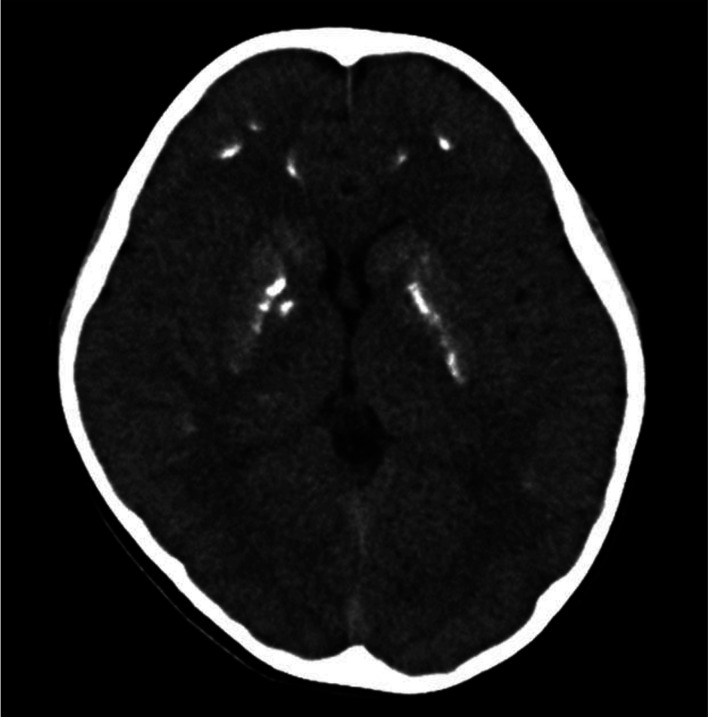

假性甲状旁腺功能减退症(PHP)是一种罕见的疾病,其特征是由于甲状旁腺激素(PTH)抵抗而导致的低钙血症引起的抽搐、四肢抽搐和感觉异常。只有少数患者会出现不自主运动。我们报告了一例患有 PHP 的 7 岁女孩,她在跑步时会出现不自主运动。起初,她被怀疑患有阵发性运动障碍,并接受了卡马西平(CBZ)治疗。不自主运动有所减少。然而,治疗两个月后,她在一次发烧时出现了抽搐。血液检查和脑计算机断层扫描显示,患者存在低钙血症、高磷血症、完整的 PTH 升高以及额叶皮层和基底节钙化。患者没有阿尔布莱特遗传性骨营养不良症的特征。停用 CBZ 并开始服用钙剂和活性维生素 D 制剂后,不自主运动消失了。对 GNAS 区域进行甲基化特异性多重连接依赖探针扩增,并对 20 号染色体进行微卫星分析,最终确诊为外显子突变引起的 PHP1B。在已报道的 15 例有或没有颅内钙化的病例中,PHP 相关的不自主运动在治疗低钙血症后消失或变得不那么严重;在 11 例中的 8 例中,运动或运动会引发不自主运动。由于血清离子钙水平降低,PHP 相关性低钙血症可诱发运动引起的不自主运动。对于这类患者,早期血液检测对 PHP 的鉴别诊断至关重要。

Pseudohypoparathyroidism (PHP) is a rare disorder characterized by convulsions, tetany, and sensory abnormalities caused by hypocalcemia due to parathyroid hormone (PTH) resistance. Only few patients present with involuntary movements. We report the case of a 7-yr-old girl with PHP and involuntary movements triggered by running. Initially, she was suspected of having paroxysmal kinesigenic dyskinesia and was treated with carbamazepine (CBZ). Involuntary movements were reduced. However, 2 months post-treatment, she experienced convulsions during a fever. Blood tests and brain computed tomography revealed hypocalcemia, hyperphosphatemia, elevated intact PTH, and calcifications in the frontal cortex and basal ganglia. The patient showed no features of Albright's hereditary osteodystrophy. The involuntary movements disappeared after the discontinuation of CBZ and initiation of calcium and active vitamin D preparations. Methylation-specific multiplex ligation-dependent probe amplification for the GNAS region and microsatellite analysis of chromosome 20 led to the diagnosis of PHP1B caused by epimutation. In 15 reported cases, with or without intracranial calcification, PHP-associated involuntary movements disappeared or became less severe with treatment for hypocalcemia; in eight of 11 cases, they were triggered by exercise or movement. PHP-associated hypocalcemia can trigger exercise-induced involuntary movements owing to lowered serum ionized calcium levels. In such patients, early blood tests are vital for the differential diagnosis of PHP.